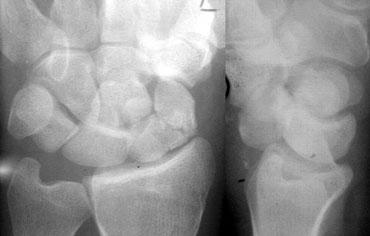

Quan sát các xương cổ tay như những mảnh ghép của trò chơi xếp hình — TRÁI: Hình minh họa sơ đồ cổ tay với các đường viền theo dõi bờ ngoài của các xương — PHẢI: Hình minh họa sơ đồ cổ tay với các đường theo dõi các xương cổ tay như những mảnh ghép xếp hình

Các khớp cổ tay cần có tính đối xứng. Hơn nữa, khi quan sát theo chiều tiếp tuyến (nhìn nghiêng), các bờ vỏ xương của các xương tạo nên khớp đó phải song song với nhau. Các bờ xương không được quan sát theo chiều tiếp tuyến sẽ không thể hiện tính song song này, ví dụ như phần xa của xương thuyền khớp với xương đầu.

Việc đánh giá tính song song này sẽ dễ dàng hơn khi xem các xương cổ tay như những mảnh ghép của trò chơi xếp hình khớp với nhau, thay vì theo dõi các xương cổ tay theo bờ vỏ xương ngoài tạo thành các đường viền (hình minh họa).

Khi một xương không song song với các xương còn lại, xương đó đã bị lệch khỏi vị trí. Nếu các xương còn lại vẫn song song với nhau, chúng vẫn giữ nguyên vị trí cùng nhau.

Hình ảnh bên trái cho thấy sự chồng lấp bất thường của xương nguyệt lên xương đầu, xương móc và xương tháp. Chúng ta cũng thấy bề mặt tiếp tuyến phía trong của xương thuyền, nhưng không có xương nào song song với nó. Ngoài ra còn có sự giãn rộng bất thường của khoang khớp quay-nguyệt. Các khớp còn lại vẫn song song và đối xứng tốt. Điều này dẫn đến kết luận rằng xương nguyệt đã bị di lệch trong khi các xương còn lại vẫn giữ nguyên vị trí cùng nhau.